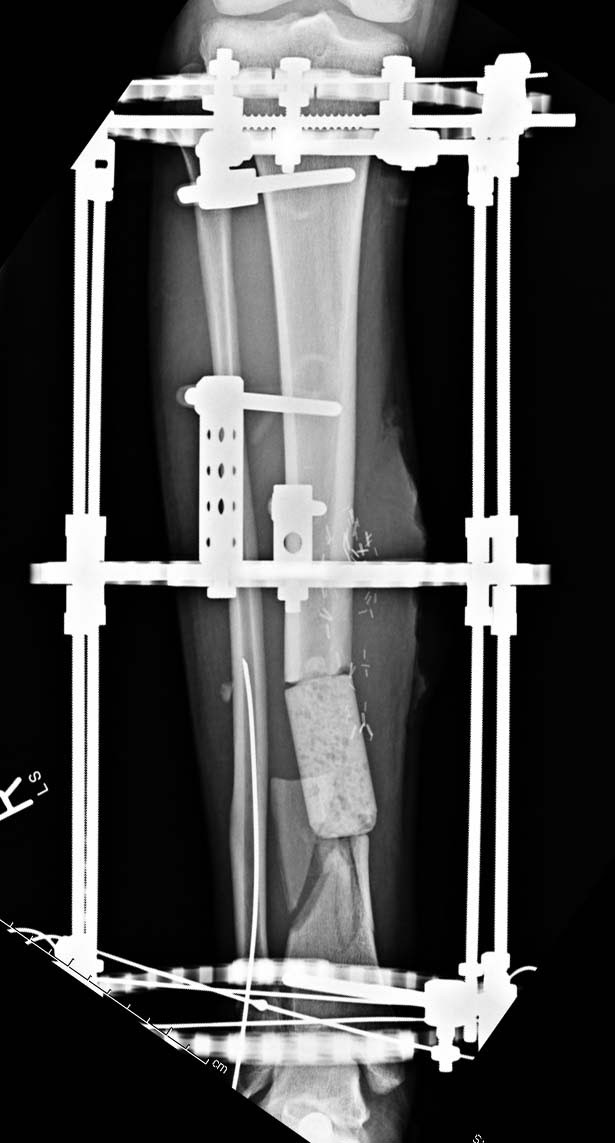

Данный случай не огнестрельная рана, а результат мотоциклетной аварии. Независимо от повреждения при таких обширных дефектах мягких и костной тканей применяется схожая тактика. Как видно, после нескольких I&D для создания “pseudo membrane” применили цилиндрический блок из цемента. Дефект мягких тканей закрыли свободным Anterior Thigh Graft. Из малого доступа цилиндр удален небольшими кусочками, а пространство заполнили бусами для освобождения пространства. По мере приближения регенерата освободили пространство удалением бус через небольшой разрез. Этап созревание регенерата можно было ускорить усилением интрамедуллярным гвоздем, но решили закончить методом Илизарова.

Теперь по поводу данного случая - “спейсер” из цемента предупреждает инфекцию и сохраняет пространство. Но вместо “бус” “цилиндрическая форма” более удобная, вокруг нее образуется ровная трубчатая поверхность “псевдо-мембраны” что в дальнейшей позволит закрыть небольшие дефекты “графтом” или во время удлинения облегчает скольжение регенерата как по трубке.